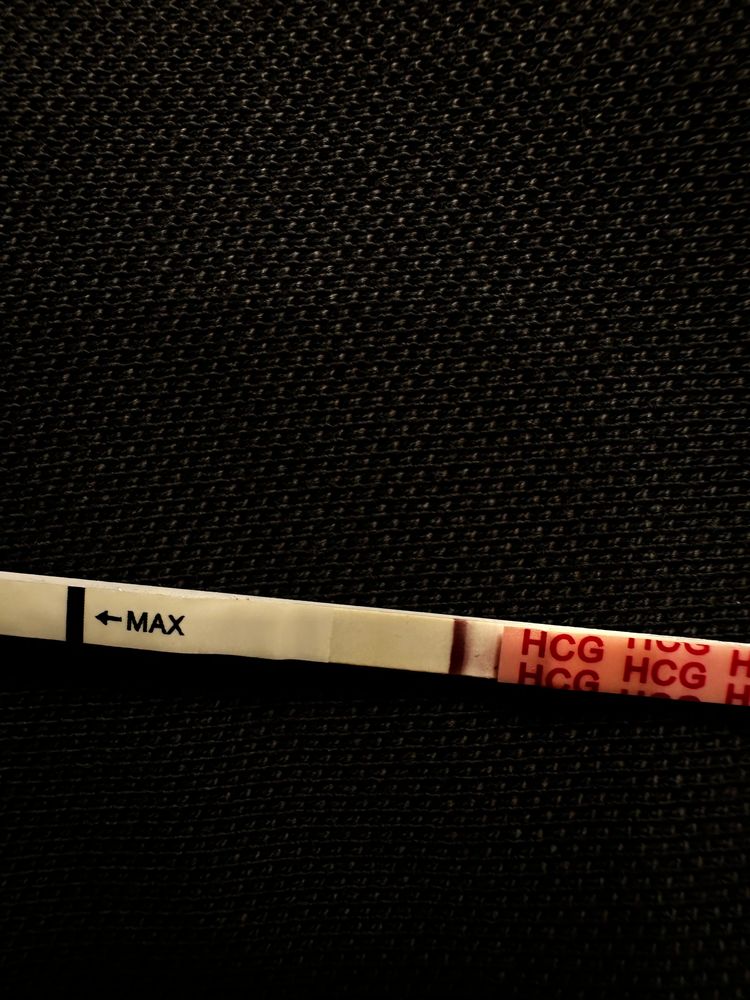

Девачки, почитала всех и короче пошла тесто манить , не могу уснуть теперь 😂😂😂😂 во что получилось напоминаю на 6 дпо

тест на о сегодняшний

Тест с верху старый 2 цикла назад

Тест с верху старый 2 цикла назад

Тест с верху старый 2 цикла назад

Тест с верху старый 2 цикла назад

Алина Горева, что-то есть, но мне кажется тест потек(

у меня в беременность именно тесты на овуляцию показали жирные // , сделала тест на б и была еле заметная полоска . Сейчас прикреплю . Но к сожалению замерла на 6 Нед

0

а тесты на овуляцию уменьшались после овуляции? Или тоже оставались насыщенными?

Алина Горева, прям сразу после овуляции? Такие жирные как у меня после 01.02? Или жирнее?)